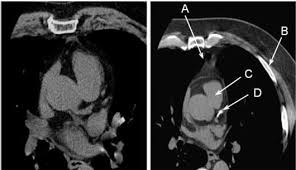

Exploración por tomografía computarizada cardíaca

Resultado de imagen de • Exploración por tomografía computarizada cardiacaSe trata de una técnica no invasiva que nos permite estudiar el estado en el que se encuentran las arterias coronarias. Durante la exploración podemos administrar contraste al paciente para obtener imágenes 3 dimensiones de las arterias coronarias y de esta manera lograr un mejor diagnóstico.